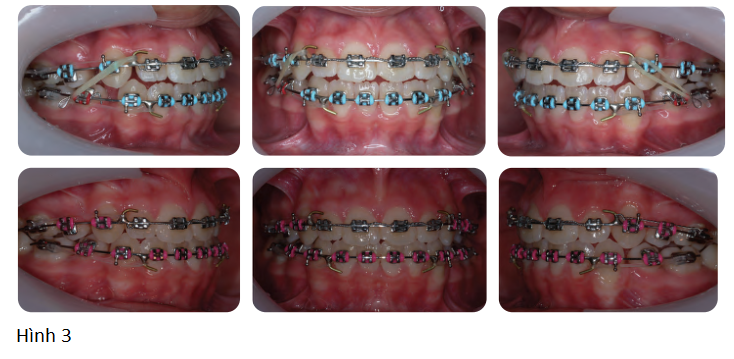

Bệnh nhân nữ 16 tuổi có sai khớp cắn hạng III trên nền xương hạng II nhẹ với tăng kích thước dọc phức tạp bởi chen chúc nhẹ và hô 2 hàm (Hình 1, Hình 2)